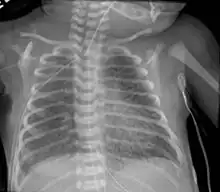

Infant respiratory distress syndrome most commonly occurs in less than six hours after birth in about 1% of all births in the United States.[9] The main risk factor is prematurity with the likelihood of it occurring going up to 71% in infants under 750g.[19] Other risk factors include infant of a diabetic mother (IDM), method of delivery, fetal asphyxia, genetics, prolonged rupture of membranes (PROM), maternal toxemia, chorioamnionitis, and male sex. The widely accepted pathophysiology of respiratory distress syndrome is it caused by insufficient surfactant production and immature lung and vascular development. The lack of surfactant makes the lungs atelectatic causing a ventilation to perfusion mismatch, lowered compliance, and increased air resistance. This causes hypoxia and respiratory acidosis which can lead to pulmonary hypertension. It has a ground glass appearance on an x-ray. Symptoms can include tachypnea, nasal flaring, paradoxical chest movement, grunting, and subcostal retractions.[9]

Pulmonary interstitial emphysema is the condition of air escaping overdistended alveoli into the pulmonary interstitium. It is a rare disease that occurs most often in premature infants, even though it is possible to appear in adults.[25] It often presents as a slow deterioration with the need for increased ventilatory support. Chest x-ray is the standard for diagnosis where it is seen as linear or cystic translucencies extending to the edges of the lungs.[9]